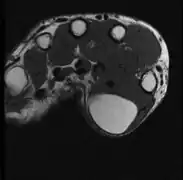

A physical exam is typically the easiest way to diagnose it. Rarely, a tissue biopsy or imaging may be required. The imaging modality of choice is magnetic resonance imaging (MRI) because it has superior sensitivity of distinguishing it from liposarcoma as well as mapping the surrounding anatomy.[22]

MRI showing lipoma of the arm -